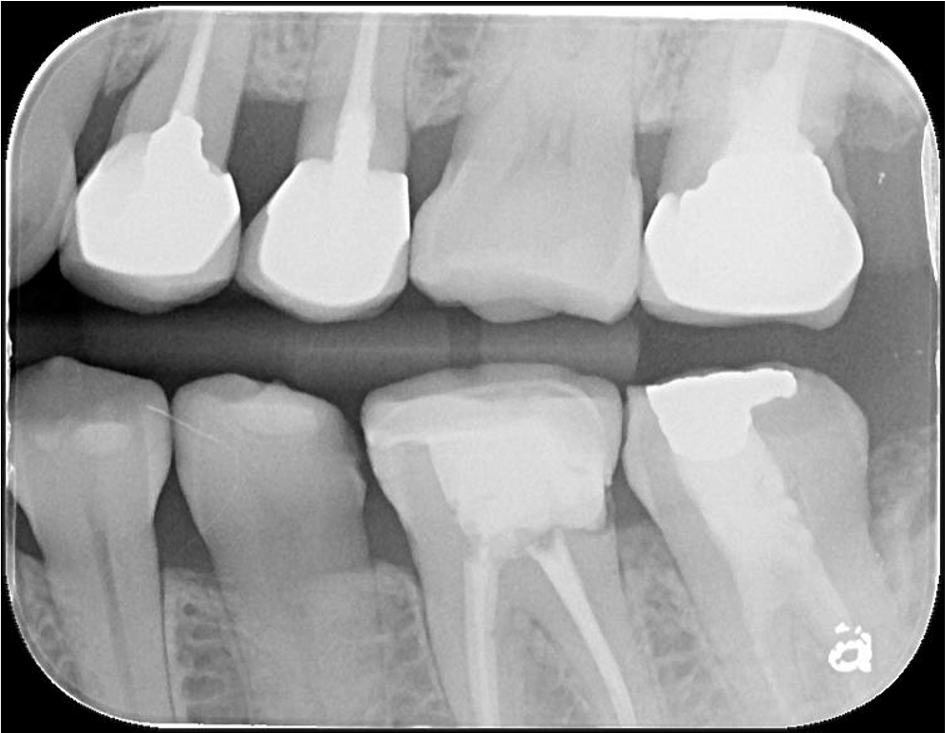

蛀牙未侵犯至牙髓

X光顯示密合度良好無殘膠